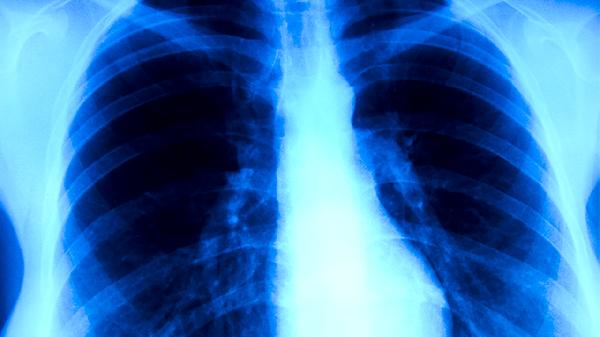

与普通肺结核相比,耐多药肺结核的病理过程更为复杂。其肺部病灶往往更广泛,容易出现空洞,组织破坏严重。细菌学上,痰涂片和培养持续阳性的时间长,治疗过程中菌阴转慢。疾病进展更快,肺内播散和肺外结核的发生概率也相对更高。